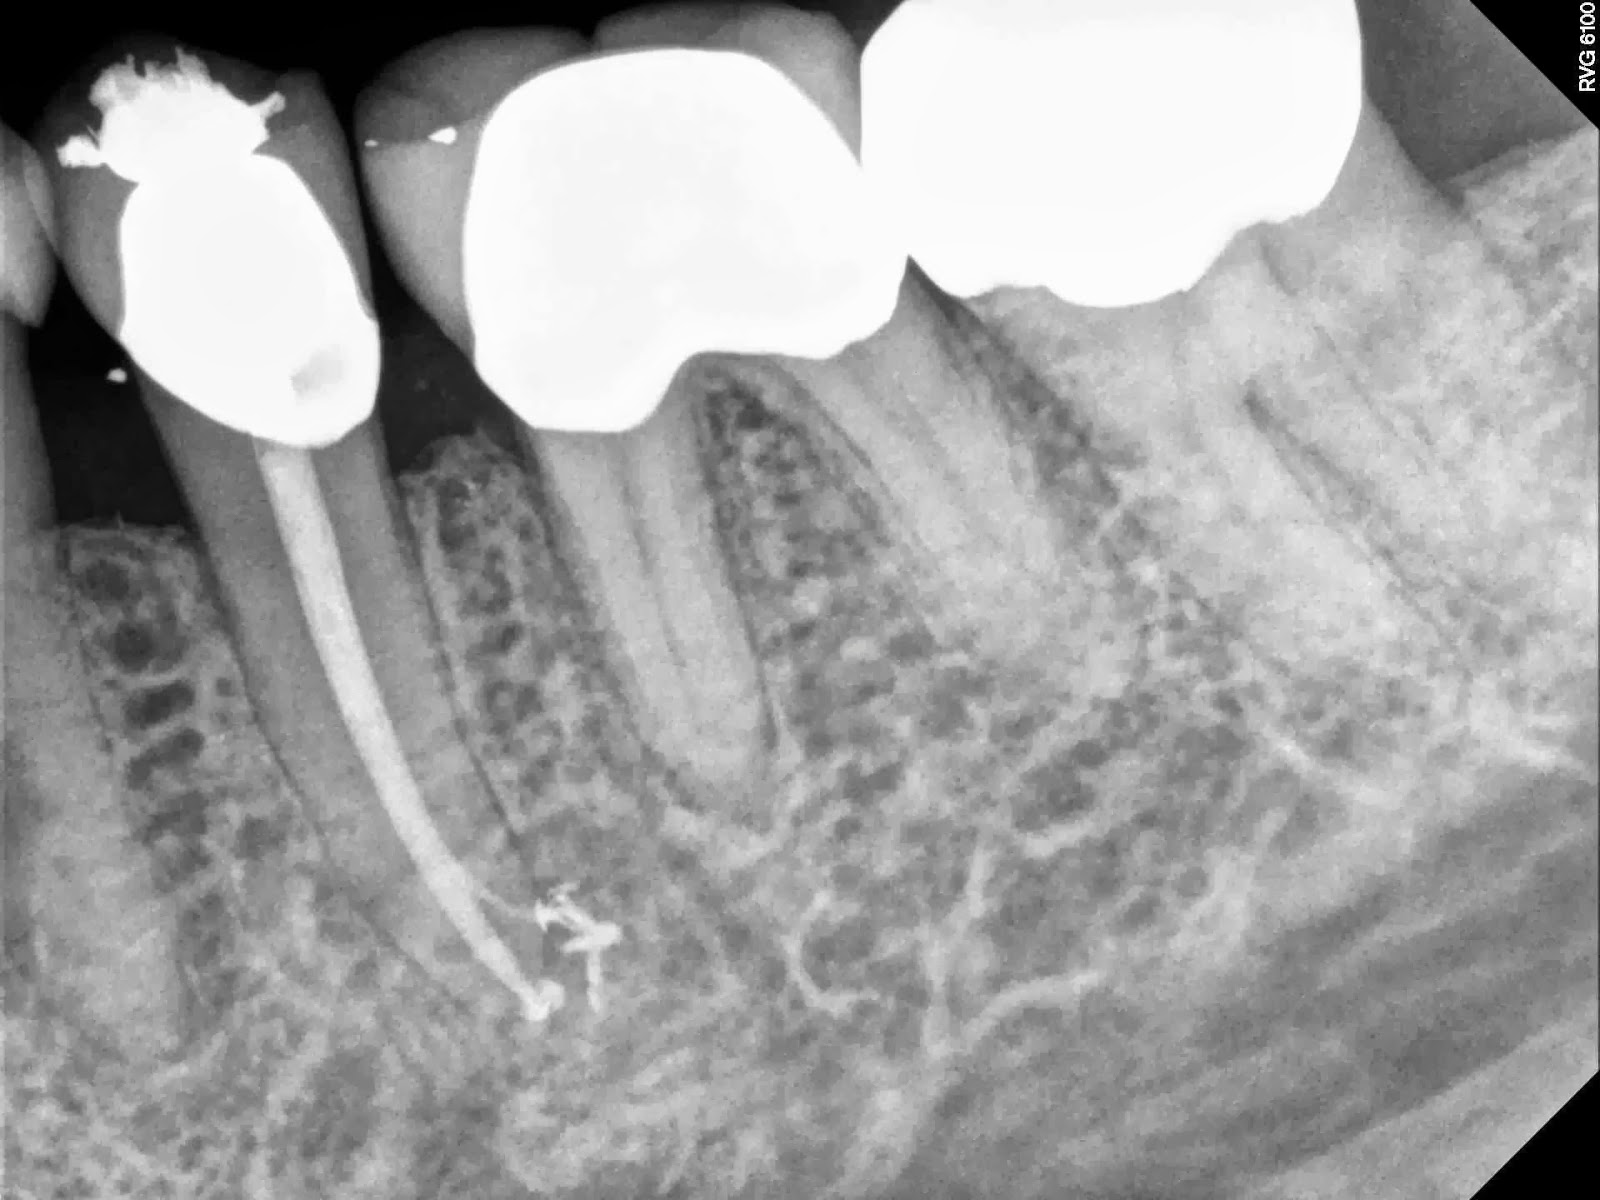

Appears to have another more cornonal lateral POE other than the one that is filled. I spent extra time with a curved 8 and 10 and lots of time with irrigants.